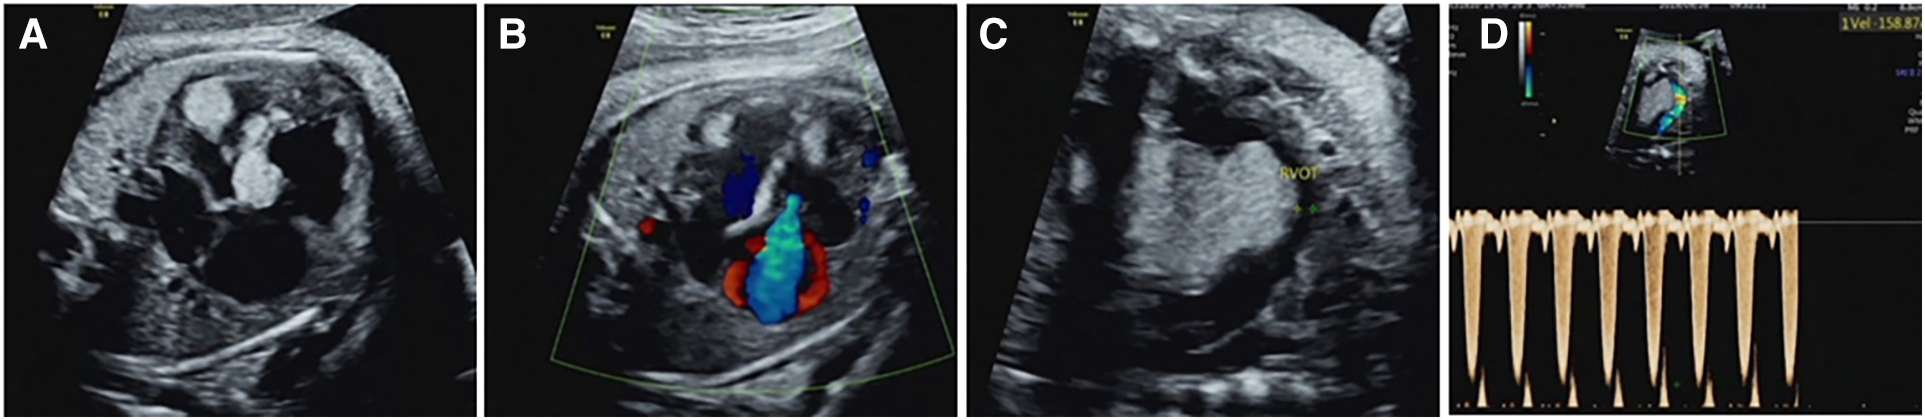

Figure 3

Intracardiac complications associated with cardiac rhabdomyoma in the fetus (case NO. 54) at 33 weeks of gestation. (A) Heart failure with cardiothoracic ratio enlargement. (B) Severe tricuspid regurgitation. (C) Rhabdomyoma located in the upper interventricular septum protrudes into the right ventricular outflow tract, resulting in a reduced internal diameter of the right ventricular outflow tract. (D) Increased velocity of the right ventricular outflow tract.

54 cases of fetal CR typically displayed round, homogeneous, high/slightly hyperechoic, intramural or intraluminal masses (Figure 2). Most cases (83.3%) had multiple lesions, with an average maximum tumor diameter of 12.26 ± 6.23 mm. Lesions were primarily found in the left ventricle (81.5%) and right ventricle (77.8%), while some appeared in the ventricular septum (42.6%), right atrium (14.8%), and left atrium (1.9%). Around 22.2% of fetuses had intracardiac complications, mainly outflow tract obstruction, arrhythmia, heart failure, pericardial effusion, or severe tricuspid regurgitation (Figure 3). The fetuses with intracardiac complications all had multiple lesions. Five fetuses had outflow tract obstruction because the tumors were located near the upper part of the ventricular septum. The mean maximum CR diameter was significantly larger in the group with intracardiac complications (17.92 ± 8.43 mm) compared to the group without complications (10.64 ± 4.37 mm) with a p-value of 0.000. This highlights the importance of lesion quantity, location, and size in causing fetal cardiac complications.